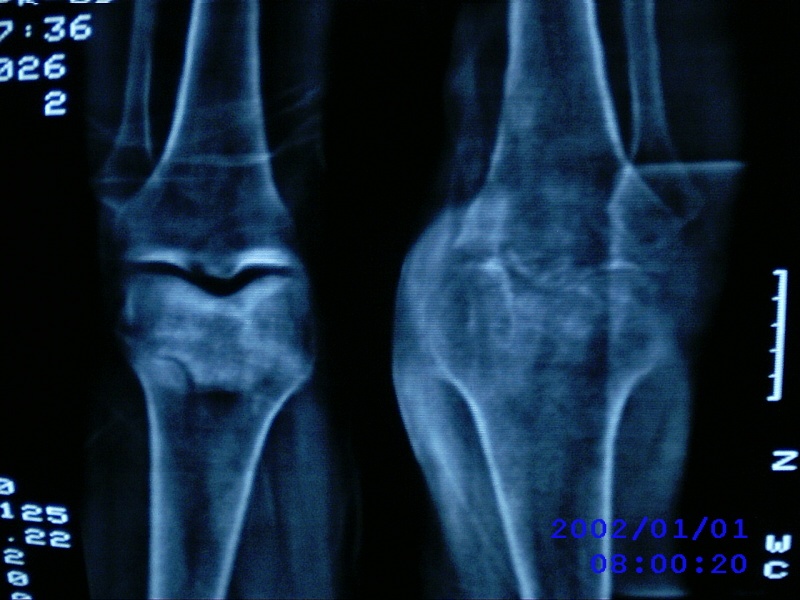

患者,男性,57岁,右侧膝关节疼痛伴肿脹10余年,加重一个月。

关节积液,关节间隙变窄,边缘骨破坏。考虑膝关节tb

关节积液,关节间隙变窄,骨质疏松,多发骨破坏,边缘轻度硬化,近端胫腓骨髓腔软组织充填,患者病史较长,支持考虑结核

有皮质的破坏~有死骨存在

多发骨破坏,骨质疏松,关节积液。考虑右膝关节结核。